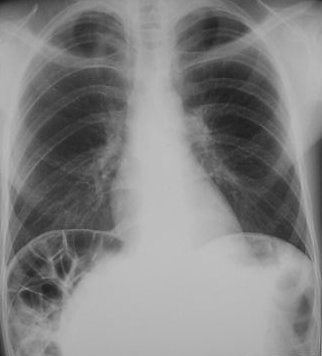

Sindromul Chilaiditi